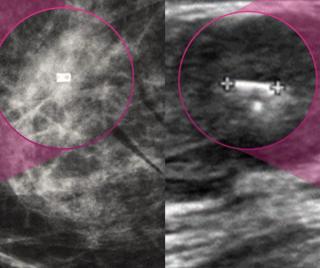

Employing a 77-second scan time for obtaining ultrafast breast MRI views, researchers found a 92.1 percent AUC for differentiating between benign and malignant lesions, according to new prospective study.